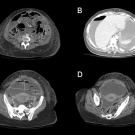

A 33-year-old postpartum woman presented to our emergency department with dyspnea, orthopnea, and generalized abdominal pain and distention for 2 days. She had been having trouble breathing at rest and had...